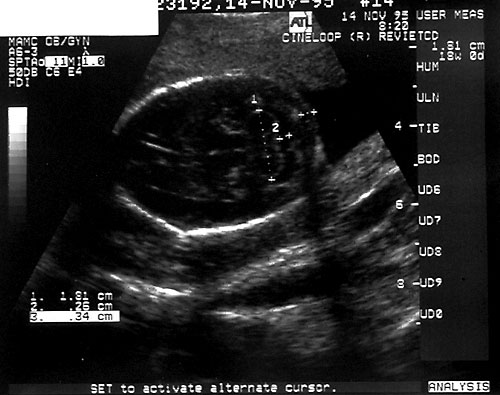

- Biparietal Diameter (BPD)/Head Circumference (HC)/Intracranial Anatomy — Ventricles/Atria/Posterior Fossa

- Accuracy is inversely related to gestational age: "one-two-three rule".

Measurements from outer edge at superior margin to inner margin at inferior margin to correct for fetal skull thickness (left). Proper measurement of head circumference (right). - Clinically meaningless, unless multiple parameters are measured and evaluated.

- Measuring BPD/HC

- Axial plane at level of septum cavum pellucidum and thalamic nuclei. (Shepard M, Filly RA. A standardized plane for bieparietal diameter measurement. J Ultrasound Med 1982;1(4):145-50.)

Normal BPD at level of thalami with cavum seen. - Falx: midline and perpendicular to angle of insonation. (Simpson GF, Filly RA. Comparison of fetal head circumference measurements using standard and long linear array transducers. J Diagn Med Sonogr 1988;4:2)